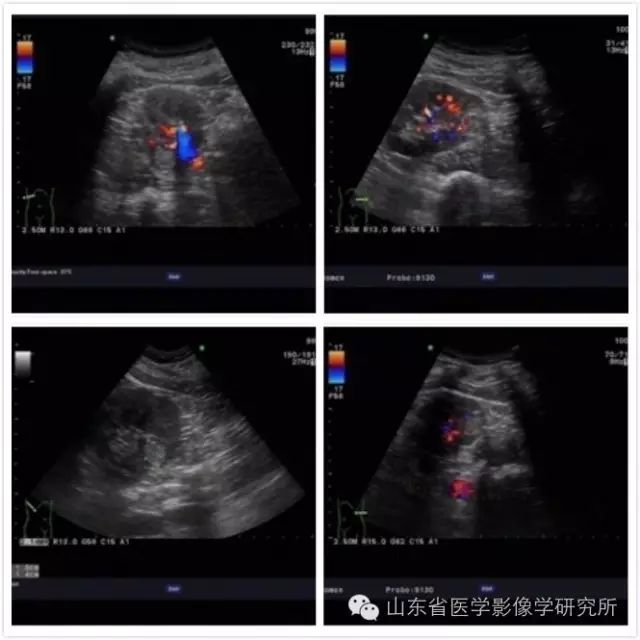

患者男性,38岁。 体检发现左肾占位。 进一步CT检查发现双肾共3个肿瘤。 影像学检查与肾癌表现一致。 这个消息对于事业处于上升期的患者来说是一个巨大的打击。 而且,由于他的双肾都有多个肿瘤,所以没有手术切除的机会。 患者来到我科后,孙耀主任精心制定了治疗方案,并两次对双肾三个肿瘤进行了消融治疗。 所有肿瘤均经病理证实为肾癌。 截至目前,肿瘤未见复发或转移。

▲术前超声检查清晰显示病灶全部

▲术后CT显示所有病灶完全消融